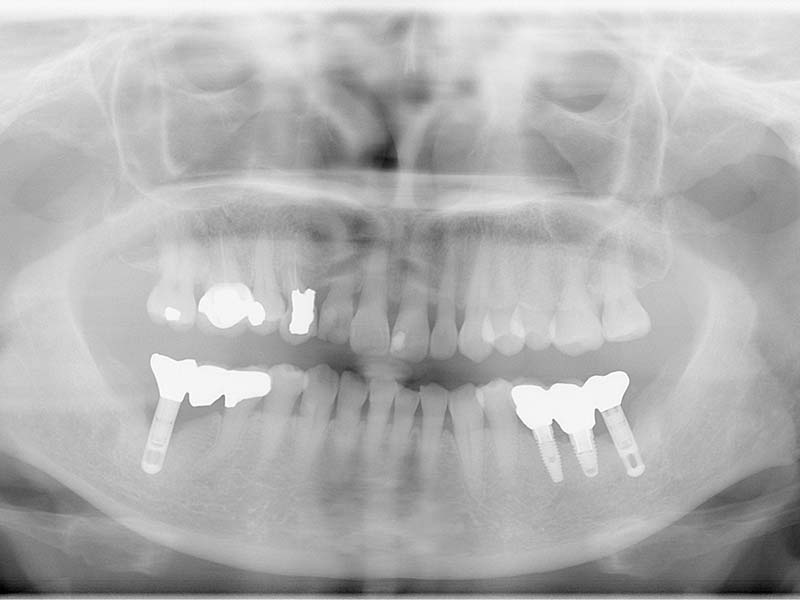

治療前

治療後